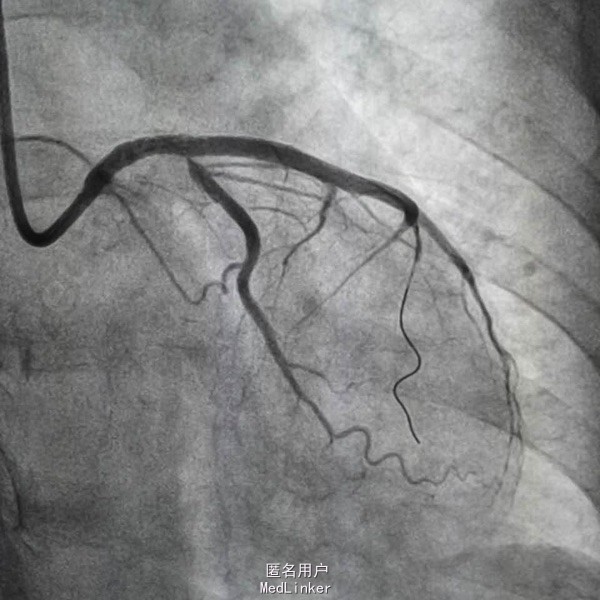

造影示左主干闭塞,如图,预扩后快速送入支架行冠脉再通,此病人心电图很难判断左主干病变,值得警惕